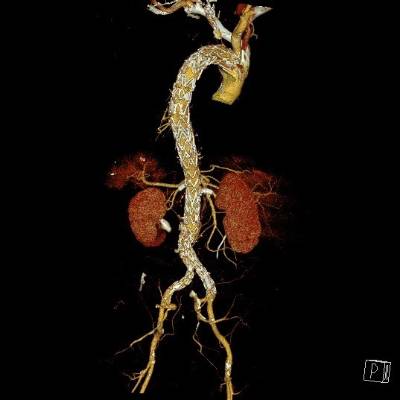

Como ejemplos de este tipo de tratamientos, "en los últimos cinco años se han implantado en el hospital seis endoprótesis ramificadas o fenestradas en pacientes con aneurismas yuxtarrenales o tóraco-abdominales. Además, el Hospital Rey Juan Carlos también realiza la técnica EVAS (Endovascular Aneurysm Sealing) para el sellado de aneurismas abdominales", explica el doctor Tomás Bolivar Gómez

, jefe asociado del Servicio de Angiología y Cirugía Vascular del Hospital Universitario Rey Juan Carlos.

La aorta es la arteria principal del cuerpo. Su trayecto se extiende desde el corazón a través del tórax y el abdomen y se divide, aproximadamente, a nivel del ombligo originando las arterias ilíacas que dan suministro de sangre a las piernas. Las arterias que irrigan los órganos tienen su origen en la aorta a lo largo de su recorrido.

"Los aneurismas son dilataciones o "globos" en alguna parte de la aorta y su principal problema es que pueden ir creciendo de forma progresiva debilitando la pared de la arteria hasta romperse. Del mismo modo, las disecciones, hematomas intramurales o úlceras penetrantes se originan por una debilidad de la pared de la aorta y pueden provocar su ruptura o bloquear el aporte de sangre a tejidos u órganos vitales, lo que se conoce como isquemia. Cuando estas enfermedades producen una afectación extensa de la aorta, combinando los segmentos torácico y abdominal, o comprometiendo el origen de sus ramas principales, la cirugía vascular ofrece soluciones mediante técnicas endovasculares basadas en catéteres, cirugía abierta convencional o una combinación de ambas", concluye el doctor Tomás Bolívar.